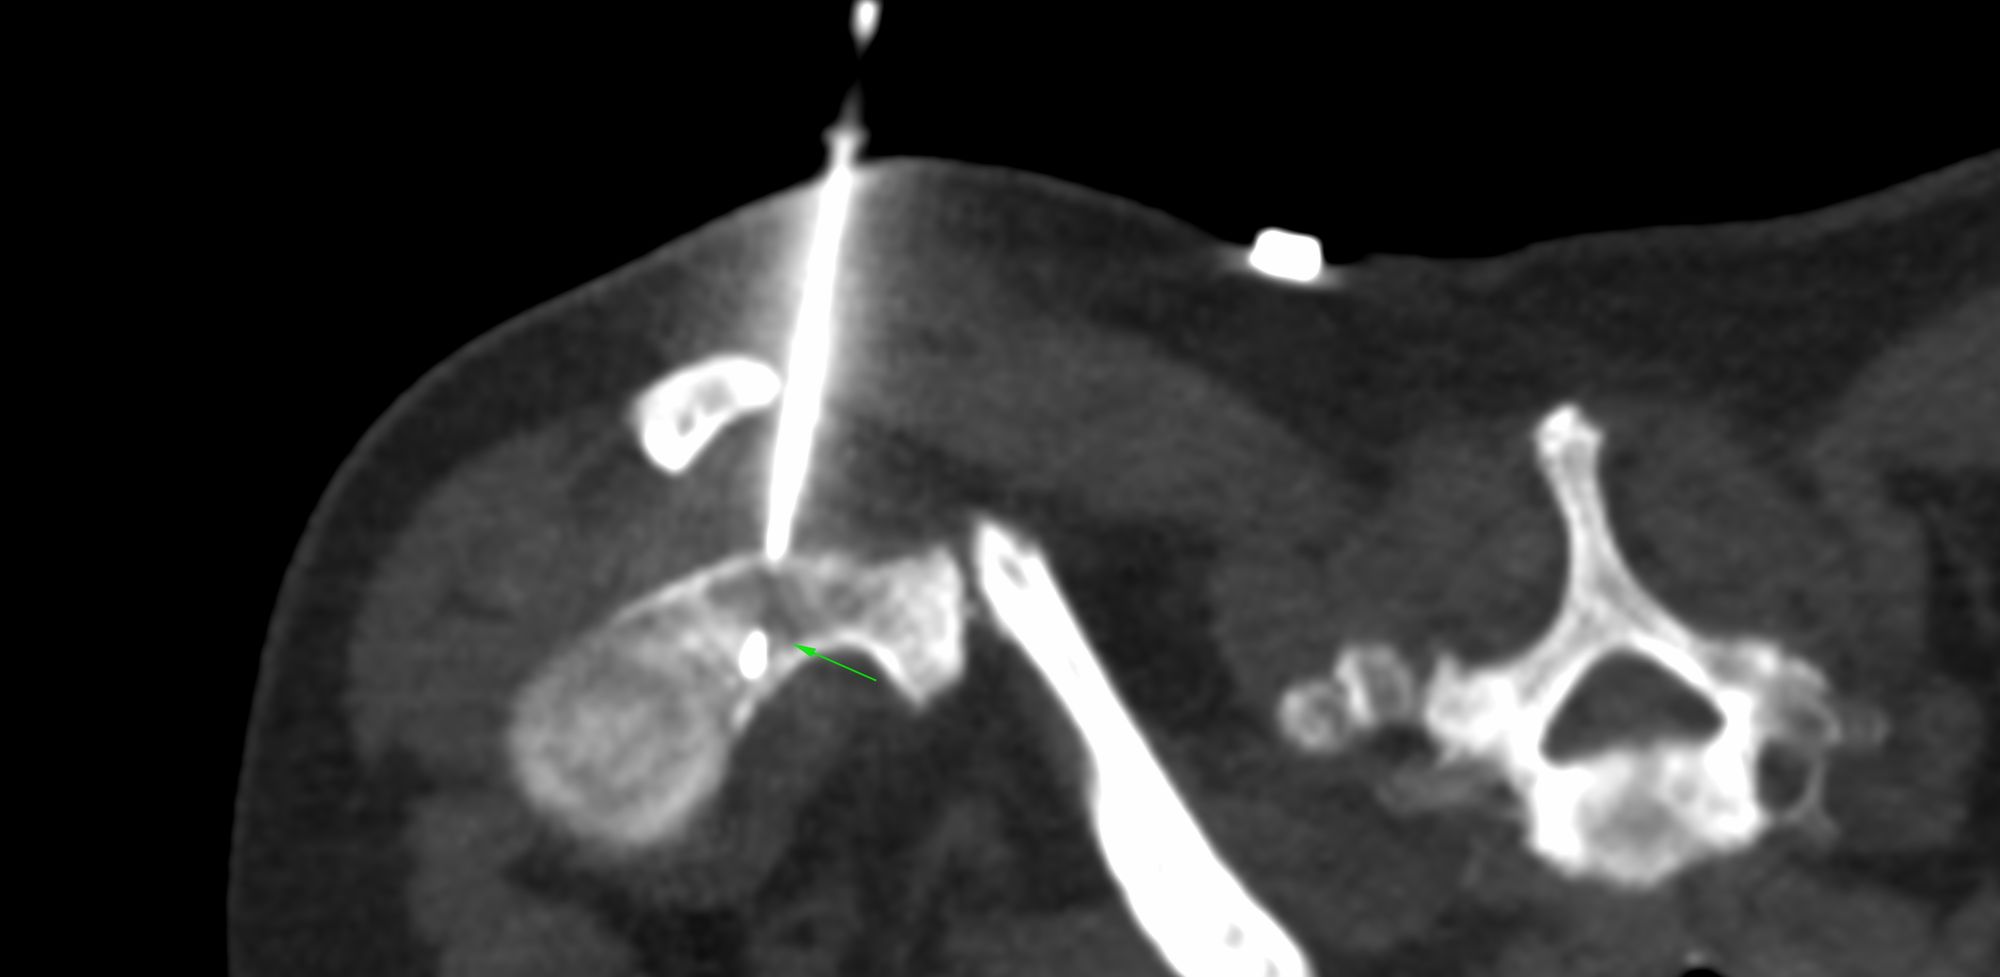

Bhavin Jankharia - 16 March 2021 Case 13: Left Mixed Osteolytic-Osteosclerotic Glenoid Bone Lesion Biopsy